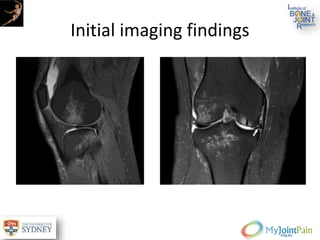

Initial imaging findings

Traumatic articular cartilage damage in

conjunction with ACL disruption.